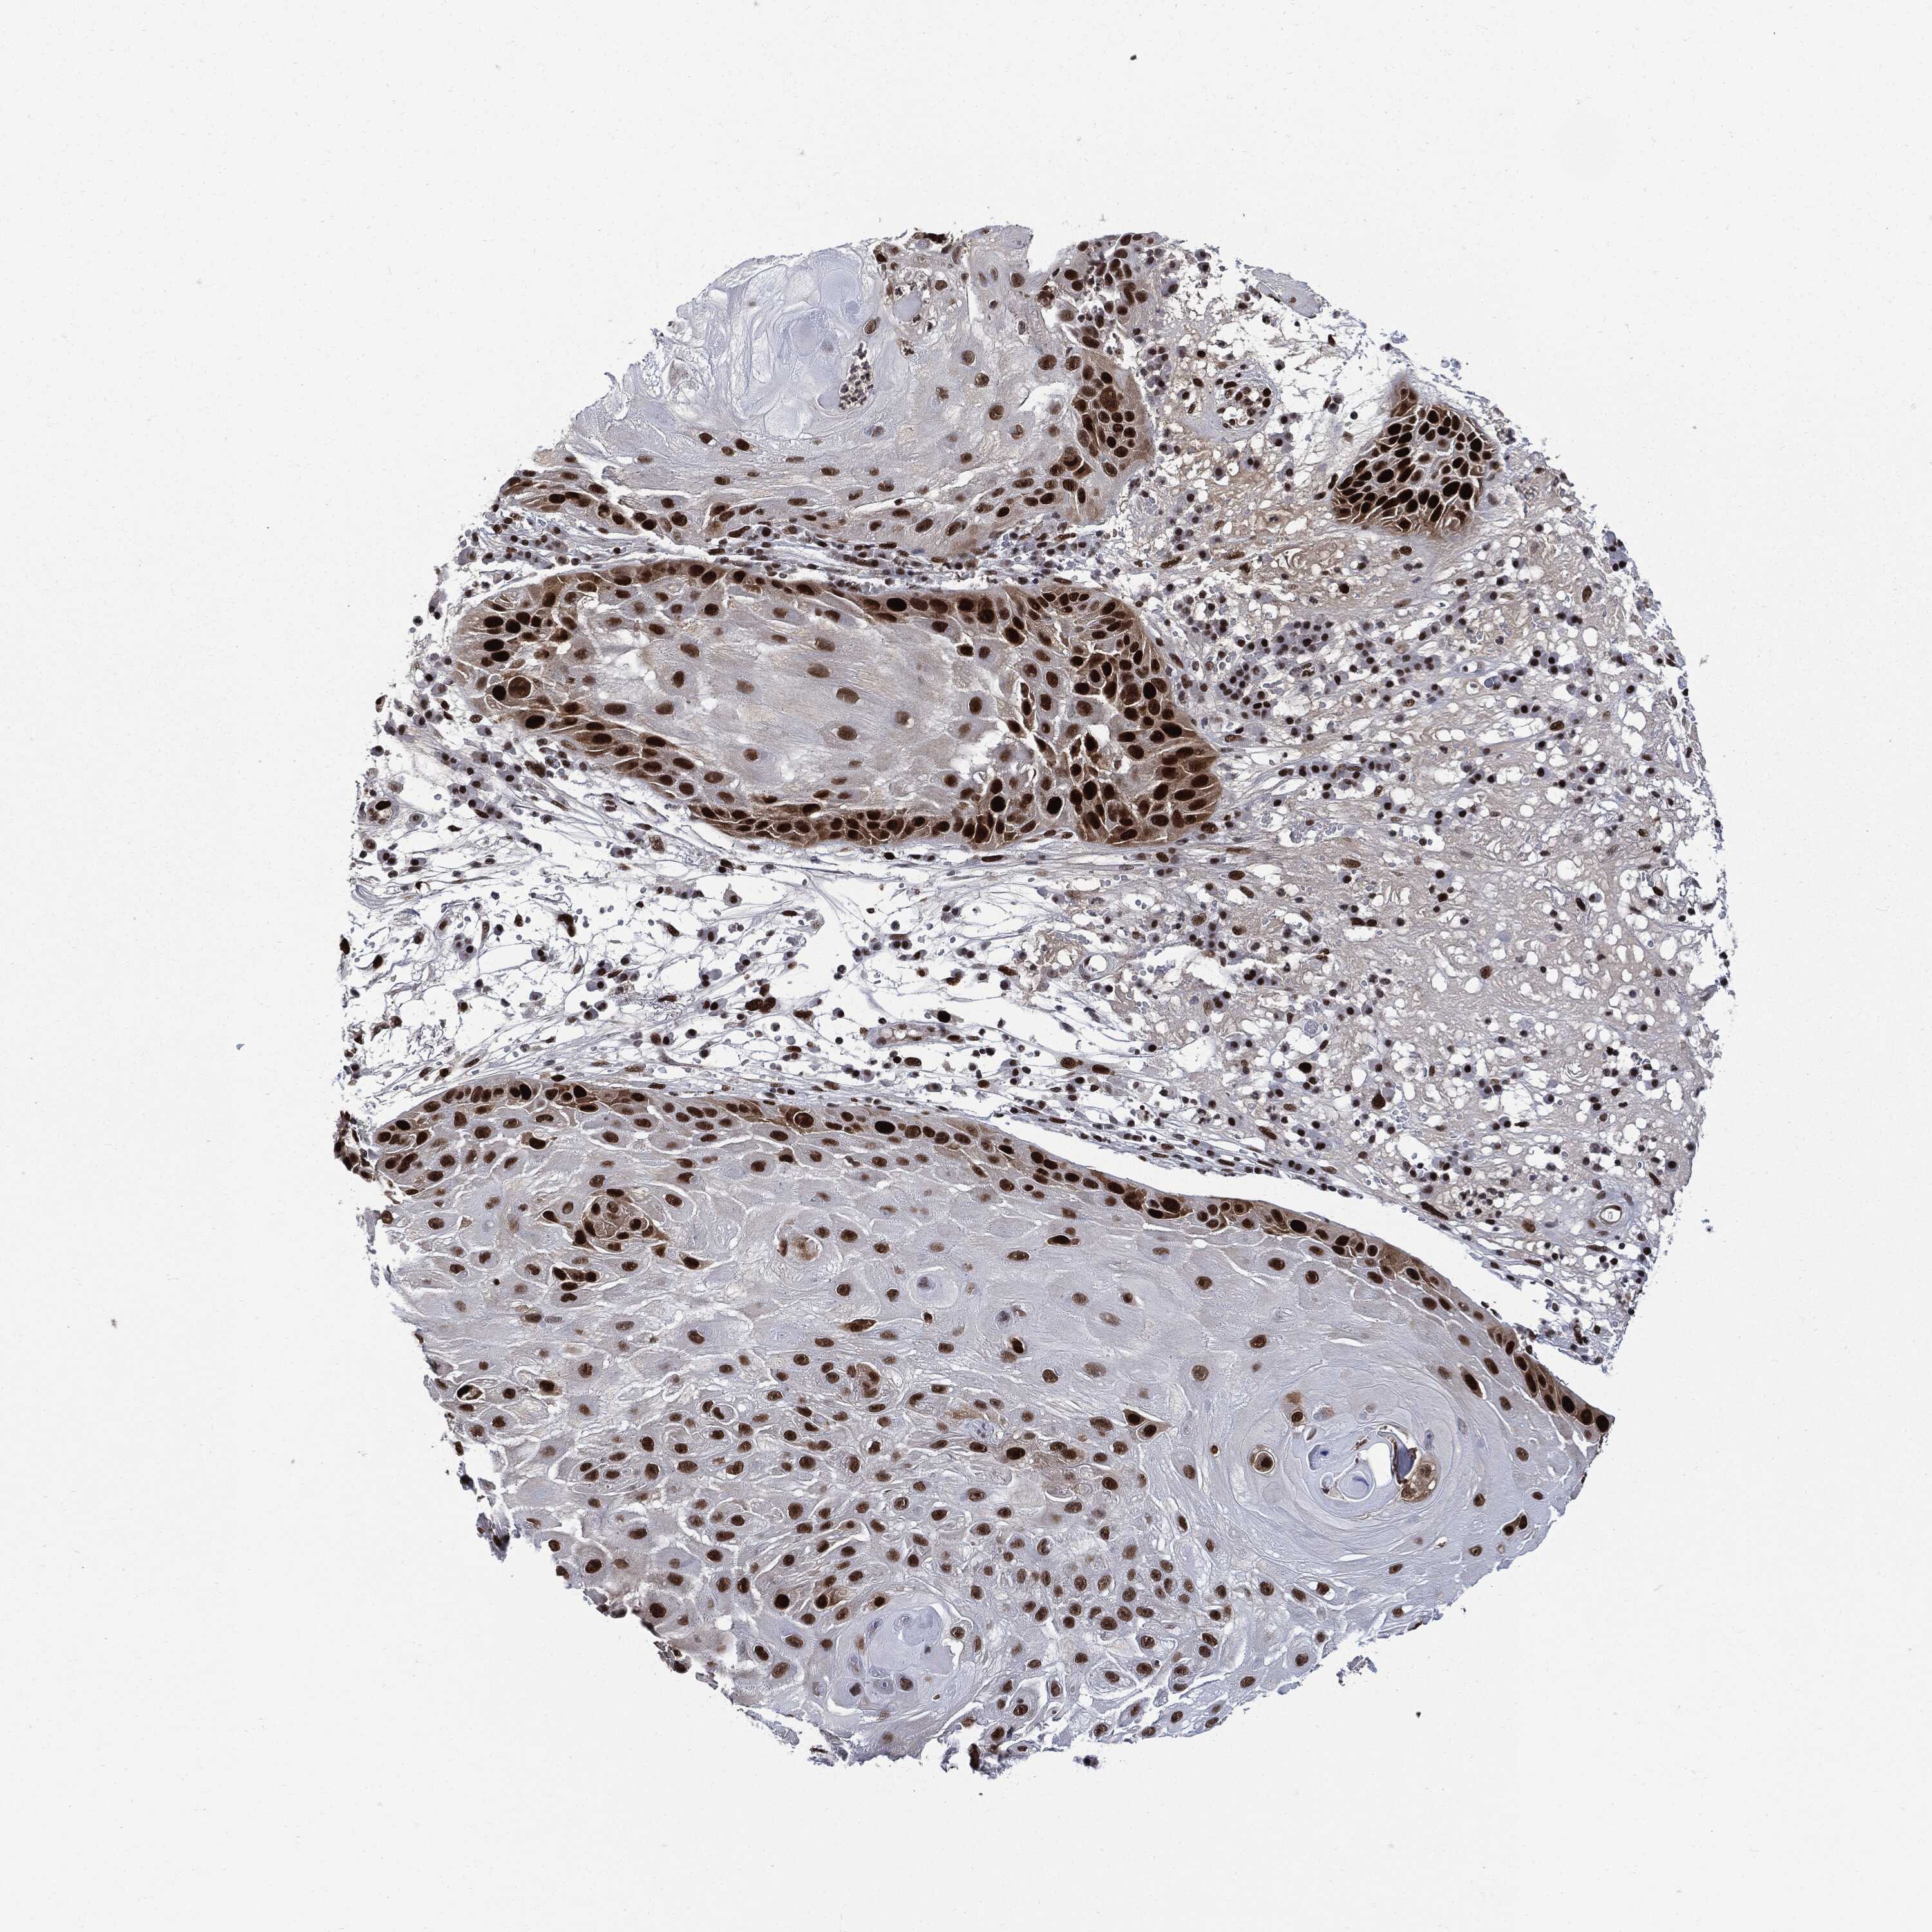

CANCER SKIN CANCER Show tissue menu

Basal cell and squamous cell cancer

SKIN CANCER - Protein expressioni

A mouse-over function shows sample information and annotation data. Click on an image to view it in a full screen mode. Samples can be filtered based on level of antibody staining by selecting one or several of the following categories: high, medium, low and not detected. The assay and annotation is described here.

Each image is clickable and will lead to virtual microscopy that enables deeper exploration of all samples and also displays staining intensity scores, fraction scores and subcellular localization as well as patient and tissue information for each sample.

HPA030521

HPA030522

HPA030523

CAB000148

CAB080240

CAB080241

CAB080242

Staining

High

Medium

Low

Not detected

Intensity

Strong

Moderate

Weak

Negative

Quantity

>75%

75%-25%

<25%

None

Location

Nuclear

Cytoplasmic/membranous

Cytoplasmic/membranous,nuclear

Basal cell carcinoma

Squamous cell carcinoma, NOS

Squamous cell carcinoma, metastatic, NOS